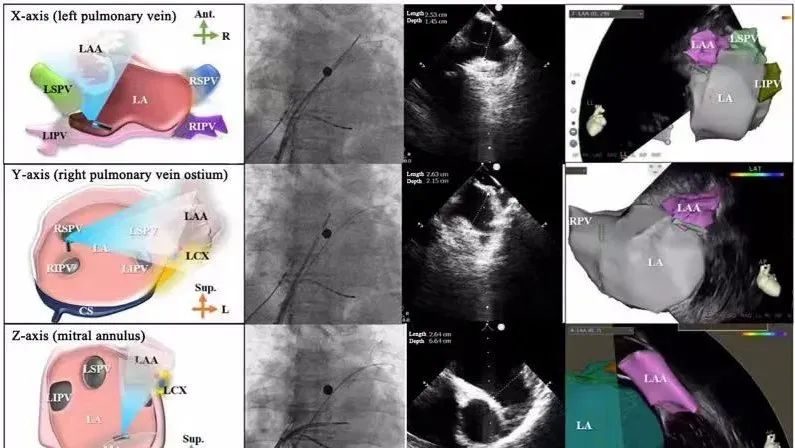

一種與心導(dǎo)管檢查相結(jié)合的超聲心動圖診斷新興技術(shù),通過將超聲探頭置于心腔內(nèi)部,發(fā)射并接收超聲信號,來精確獲取心臟解剖結(jié)構(gòu)、心臟血流動力學(xué)等信息的實時成像。與其他影像技術(shù)相比,ICE技術(shù)具有操作簡單、無輻射、安全性高、手術(shù)效率高、實用等優(yōu)勢,ICE在很大程度上有望取代經(jīng)食道超聲心動圖(TEE),成為電生理和結(jié)構(gòu)性心臟病領(lǐng)域的理想成像方式。

目前ICE技術(shù)已被應(yīng)用于左心耳封堵、房顫射頻消融、二尖瓣成形、房間隔缺損封堵等多種心臟介入手術(shù),應(yīng)用場景主要圍繞心臟電生理、結(jié)構(gòu)性心臟病等領(lǐng)域,目前以電生理應(yīng)用為主。數(shù)據(jù)顯示,我國結(jié)構(gòu)性心臟病介入器械市場規(guī)模已從2017年的4億元增長至2021年的20億元,年復(fù)合增長率達48.3%;預(yù)計到2025年,該市場規(guī)模將達到104億元,可以預(yù)見ICE市場規(guī)模也將同步高速增長,未來市場發(fā)展空間廣闊。

心腔內(nèi)超聲(ICE)技術(shù)壁壘極高,國內(nèi)主要廠商核心部件仍舊為進口,集成了超聲和圖像處理最前端技術(shù),包括超聲探頭、線纜、軟件成像算法等,是當(dāng)前內(nèi)窺超聲方向最具挑戰(zhàn)的領(lǐng)域。ICE的應(yīng)用經(jīng)歷了2D平面成像、3D三維立體成像、以及4D的實時三維立體成像階段。